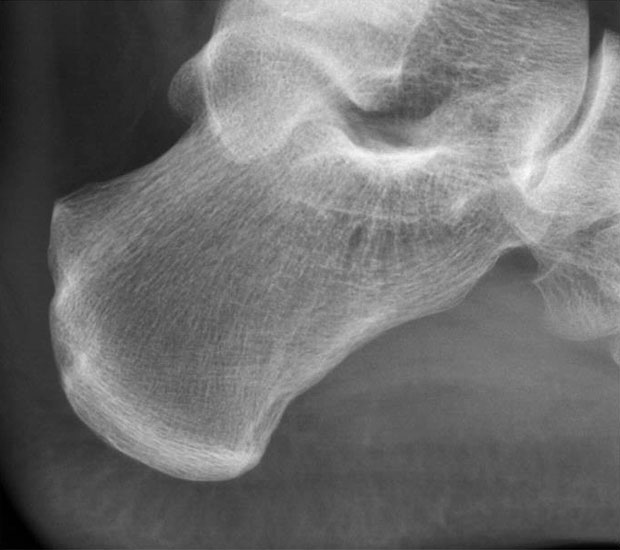

Abbildung 11-12

Prä- und postoperatives Röntgenbild.